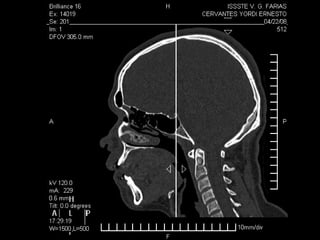

Tomografía computarizada

De seno maxilar corte sagital.

Area de implantación

Dentaria.

Material osteoconductor

para elevar el piso antral

Nuevo piso del seno y su

margen de seguridad para

contener el implante

Tomografía computarizada De senomaxilar corte sagital. Area de implantación Dentaria.

Nuevo piso delseno y su margen de seguridad para contener el implante dentario